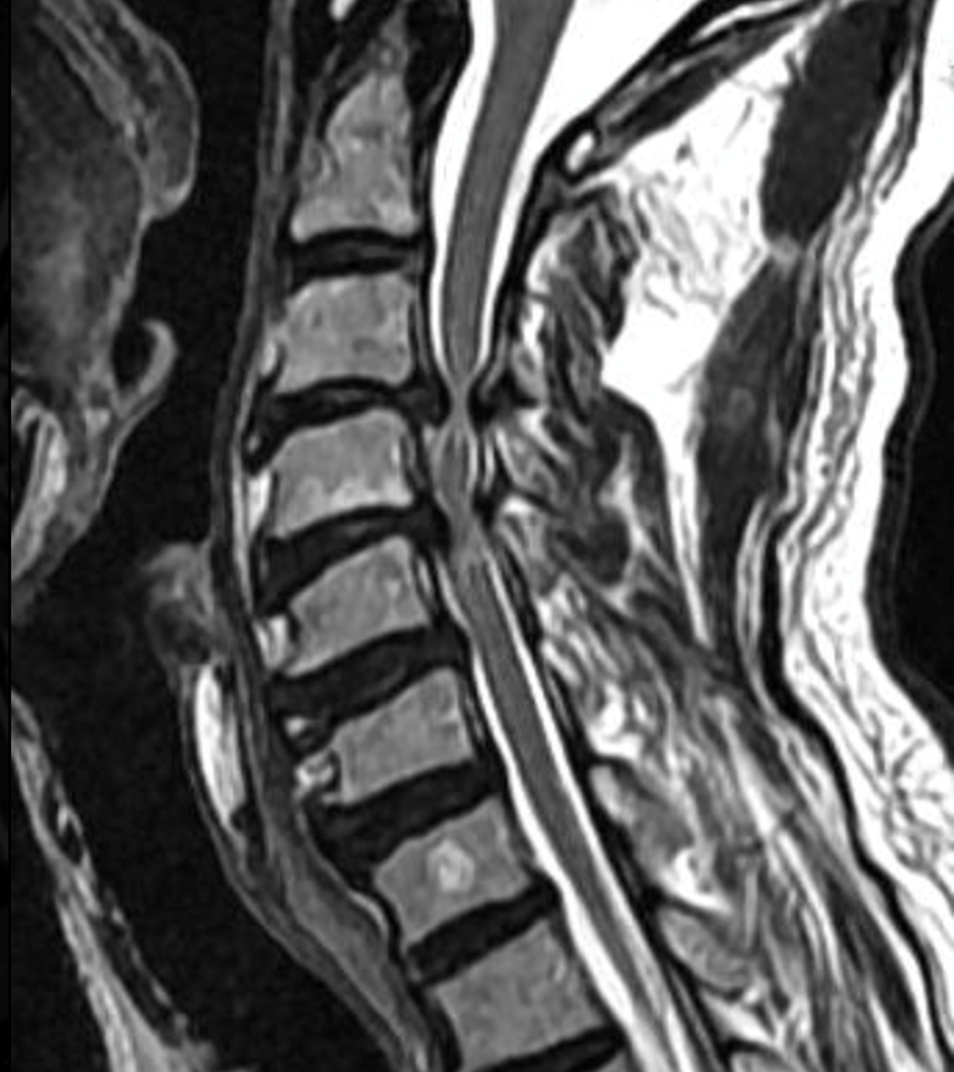

A 66-year-old man presented with several falls over the course of the past few months. On examination, he had symmetrical weakness of his legs and mild weakness of his hand. He had an abnormal gait. His reflexes were extremely brisk in his legs with upgoing planters bilaterally. He has positive Hoffman’s sign. What is the most likely diagnosis?

Degenerative cervical myelopathy due to cervical spondylosis